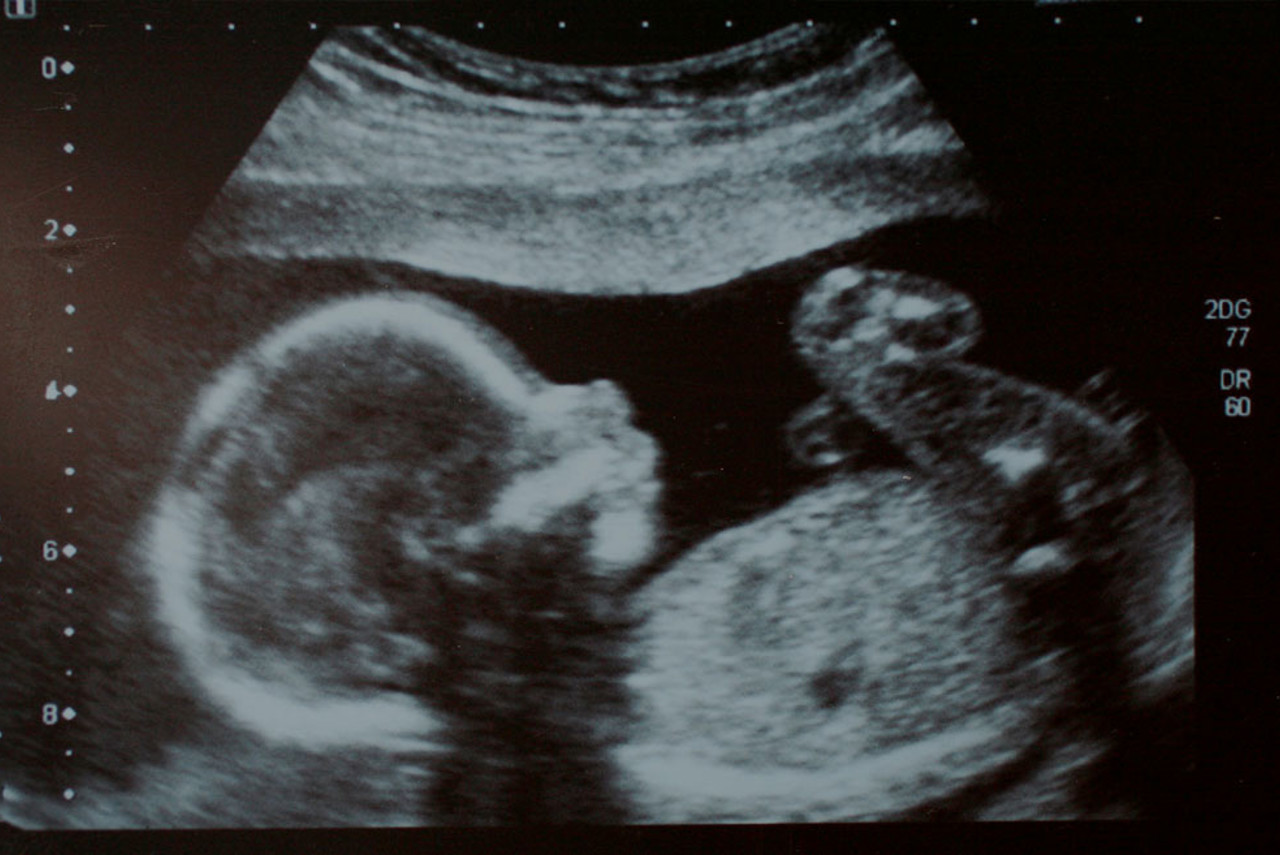

A Nuchal Translucency scan looks at the fluid at the back of the baby’s neck. The amount of fluid can be indicative of chromosomal abnormalities or cardiac conditions.

The timing of this scan is important as the fluid in the neck generally gets reabsorbed by the body after 14 weeks of gestation.

During a nuchal translucency scan, the sonographer will perform multiple measurements, including the fluid at the back of the baby’s neck.